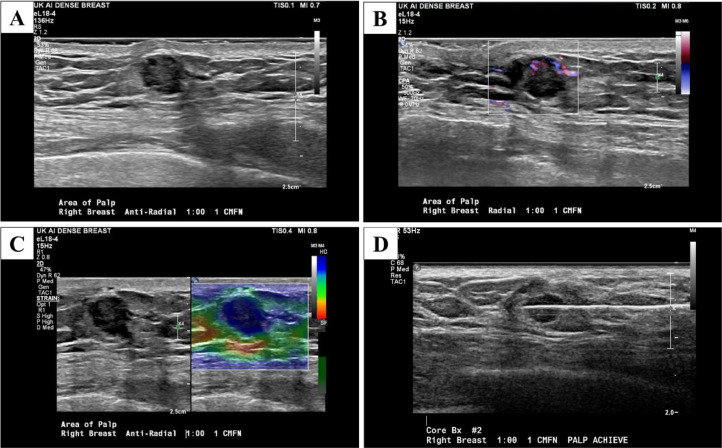

There is a mild enlargement of the right axillary lymph nodes (Fig. 6). A focused ultrasound was obtained for further evaluation of right breast mass. A round, isoechoic, mass with indistinct margins, and internal vascularity measuring 12 mm in the right breast at 1-o'clock located 1 cm from the nipple was observed (Fig. 7). Elastography was used and showed the mass was hard (Fig. 7).

Fig. 7.

Focused ultrasound in the right breast in the area of palpable concern showed a single round 12×8×9 mm hypoechoic mass in the 1: 00 position 1 cm from the nipple (A), which has increased blood flow on the Doppler ultrasound (B) and is hard on the elastography (C) Ultrasound-guided core biopsy with a 14-gauge needle was done in the left breast at 1-o'clock and 1 cm from the nipple (D).

A focused ultrasound was performed in the right axilla in transverse and longitudinal planes. There were a few abnormal lymph nodes in the right breast. Ultrasound-guided core biopsy was performed (Fig. 7), and a biopsy clip was placed in the right breast. A fine needle aspiration was performed in the lymph node of the right axilla.